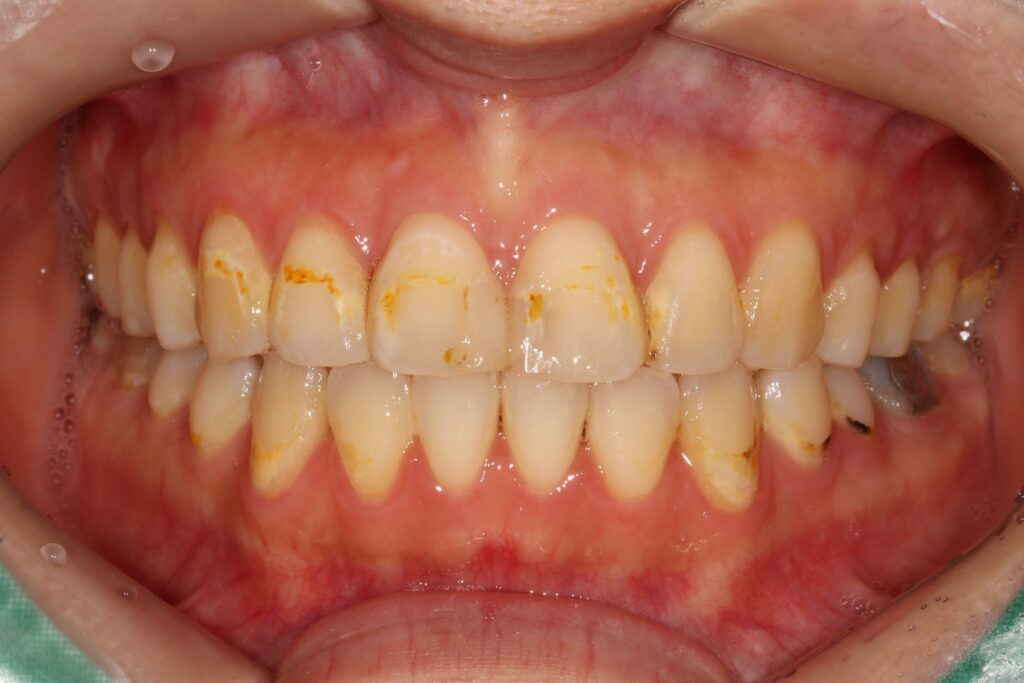

먼저 심미적인 개선이 가장 중요한

위쪽 송곳니부터 송곳니까지

총 6개의 전치부에 대해 e.max empress

라미네이트 베니어를 적용하였습니다.

이를 통해 치아의 색상과 형태를

자연스럽게 개선하고,

전체적인 조화를 맞추는 데 중점을 두었습니다.

이어서 나머지 치아에서는 치경부 우식 부위를

중심으로 복합레진 수복을 시행하여

손상된 부위를 보존하고 추가적인 진행을 방지하였습니다.

또한 우식 범위가 넓거나 교합 부담이

큰 부위에는 인레이 치료를 적용하여

내구성을 확보하였고,

치수까지 영향을 받은 치아에 대해서는

근관치료를 선행한 후 크라운으로

최종 수복을 진행하였습니다.

전체적으로 인레이 6개, 근관치료 1개,

크라운 2개, 레진 6개 등 총 20개 치아에 대한

치료가 이루어졌으며,

이를 통해 심미적인 개선과 더불어

기능적인 안정성까지 함께

확보할 수 있었습니다.

치료 후에는 치아의 색상과 배열,

형태가 자연스럽게 어우러지며

환자의 만족도를 높일 수 있었습니다.